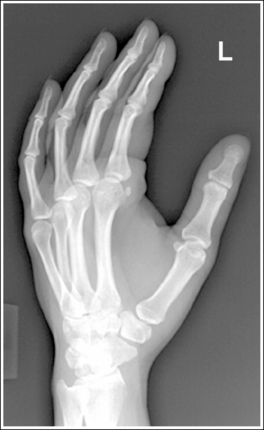

Hand: “Fan” Lateral Projection (Lateromedial)

See Figure 4-27 and Box 4-10.

Density is adequate to demonstrate the surrounding metacarpal soft tissue and bony structures of the hand.

• For the fan lateral hand projection, it is difficult to demonstrate the phalanges and the metacarpals with optimal density simultaneously because of the difference in thickness between the two body parts when the fingers are separated. Evaluate the requisition to determine which anatomy of the hand is of interest so that the mAs can be adjusted to obtain optimal density in that area.

The second through fifth digits are separated, demonstrating little superimposition of the proximal bony or soft tissue structures. The thumb is demonstrated without superimposition of the other digits. Its position may vary from a PA projection to a slight PA oblique projection.

• For a lateral hand projection, place the medial hand surface resting against the IR; then fan or spread the fingers as far apart as possible without superimposing the thumb. The fingers are fanned most effectively by drawing the second and third fingers anteriorly and the fourth and fifth fingers posteriorly. The amount of finger separation obtained will depend on the patient's mobility (Figure 4-28). Immobilization devices are available to help maintain proper positioning. When the fingers are fanned, they can be individually studied. If the fingers are not adequately separated, they superimpose one another on the image (see Images 26 and 28).

Image 26

The second through fifth metacarpals are superimposed.

• Superimpose the second through fifth metacarpals by palpating the patient's knuckles and placing them directly on top of one another.

• Verifying a lateral hand projection. On a lateral hand projection, a true lateral wrist position, represented by superimposition of the ulna and radius, is not always accomplished when the metacarpal midshafts are superimposed. Instead, the ulna is demonstrated slightly posterior to the radius. Because of this variation, a true lateral projection of the hand should be determined by judging the degree of superimposition of the second through fifth metacarpal midshafts and not the degree of ulnar and radial superimposition. If the metacarpal midshafts are not superimposed and the fifth metacarpal is demonstrated anterior to the second through fourth metacarpals, the hand was slightly externally rotated or supinated (see Image 26). The fifth metacarpal can be identified by its length; it is the shortest of the second through fifth metacarpals. If the metacarpal midshafts are not superimposed and the second metacarpal is demonstrated anterior to the third through fifth metacarpals, the hand was slightly internally rotated or pronated (see Images 27 and 28). The second metacarpal can also be identified by its length; it is the longest.

Image 27

The IP joints are open, and the phalanges are not foreshortened.

• The IP joint spaces are open and the phalanges are visible without foreshortening when the thumb is depressed and all the digits are positioned parallel with the IR.

The MP joints are at the center of the exposure field. The distal, middle, and proximal phalanges, the metacarpals, the carpals, and approximately 1 inch (2.5 cm) of the distal radius and ulna are included within the collimated field.

• Center a perpendicular central ray to the second MP joint to place it in the center of the collimated light field. Once the central ray is centered, open the longitudinal collimation to include the distal phalanges and the distal forearm. Transversely collimate to within 0.5 inch (1.25 cm) of the first and fifth finger's skin line.

• Either half of a 10- × 12-inch (24- × 30-cm) detailed screen-film IR placed crosswise or a single 8- × 10-inch (18- × 24-cm) screen-film or computed radiography IR placed lengthwise should be adequate to include all the required anatomic structures.

The second through fifth metacarpal midshafts are not superimposed, and the shortest (fifth) metacarpal is anterior to the third through fourth metacarpals. The hand was externally rotated. This image may also result if the central ray was positioned anterior to the MP joints to increase transverse collimation.

Internally rotate the patient's hand until the metacarpals are superimposed. Center the central ray to the MP joints.

The second through fifth metacarpal midshafts are not superimposed, and the longest (second) metacarpal is anterior to the third through fifth metacarpals. The hand was internally rotated.